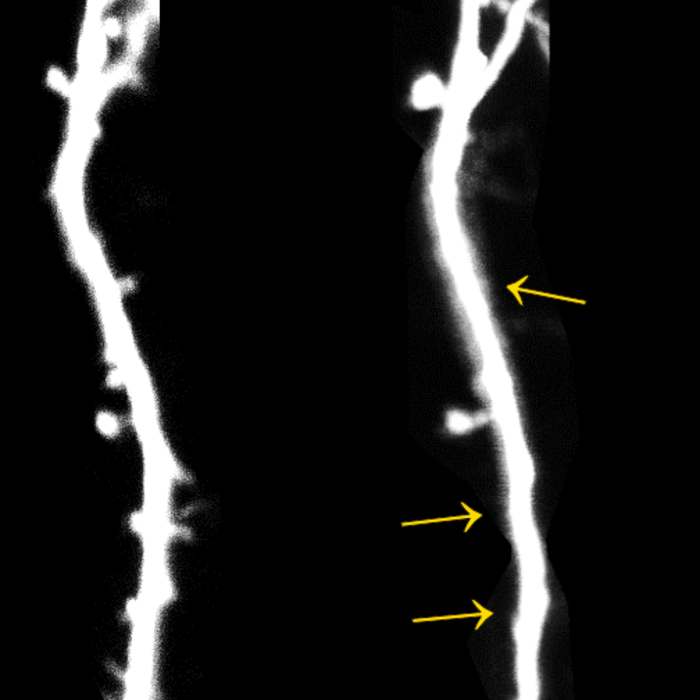

The researchers used mice as experimental animals, some of which they exposed to a stressful situation for a few days. Meanwhile, they used a special microscopy method to take pictures of the rodents' brains. They focused on parts of the cerebral cortex responsible for motor control and learning new movements.

"With our method, it is possible to observe one and the same neuron at different points in time," says Dr. Anne-Kathrin Gellner, a physician at the Department of Psychiatry and Psychotherapy at Bonn University Hospital. "We can therefore see whether and how it changes as a result of stress."

In fact, the researchers came across a conspicuous feature: after the stressful situation, the neurons studied lost some of their synapses - these are the contacts to other nerve cells. During learning processes, new synapses are usually formed or existing ones are strengthened. Instead, the stressed rodents lost up to 15 percent of their contacts.

Even in resilient animals, moreover, the number of synapses decreased after the stress event. Unlike their stress-sensitive peers, however, the affected neurons recovered: after one and a half weeks, the number of synapses was again similar to that before the stress event and comparable to that in non-stressed control animals. "Nevertheless, it may well be that psychological stress also leaves permanent traces on them if it is too long or too frequent," worries Stein, who is also a member of the Transdisciplinary Research Area (TRA) "Life and Health."

The researchers also have clues as to what triggers the loss of synapses: Certain immune cells, the microglia, were activated in the rodents' brains. They belong to the so-called phagocytes and can, for example, digest pathogens or defective cells. It is possible that they are "switched on" by stress and then attack the contact sites.